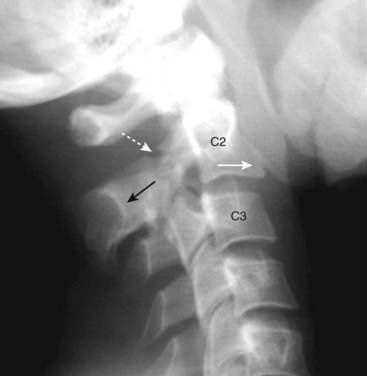

image They are best evaluated on the lateral view of the cervical spine on conventional radiography and the sagittal view on CT.

imageThe fracture effectively separates the posterior aspect of the C2 vertebral body from the anterior aspect of C2 allowing the anterior aspect of C2 to sublux forward on the body of C3 (Fig. 24-19).

image

Figure 24-19 Hangman’s fracture.

A hangman’s fracture results from a hyperextension-compression injury. It involves fractures through the posterior elements of C2 best evaluated on the lateral view. The fracture (dotted white arrow shows fracture line) effectively separates the posterior aspect of the C2 vertebral body from the anterior aspect of C2 allowing the anterior aspect to sublux forward on the body of C3. Notice that the spinolaminar line of C2 lies posterior to the other vertebral bodies (solid black arrow) and the anterior aspect of C2 lies forward of the anterior body of C3 (solid white arrow).

Some hangman fractures are less displaced, so that CT may be needed for their detection.